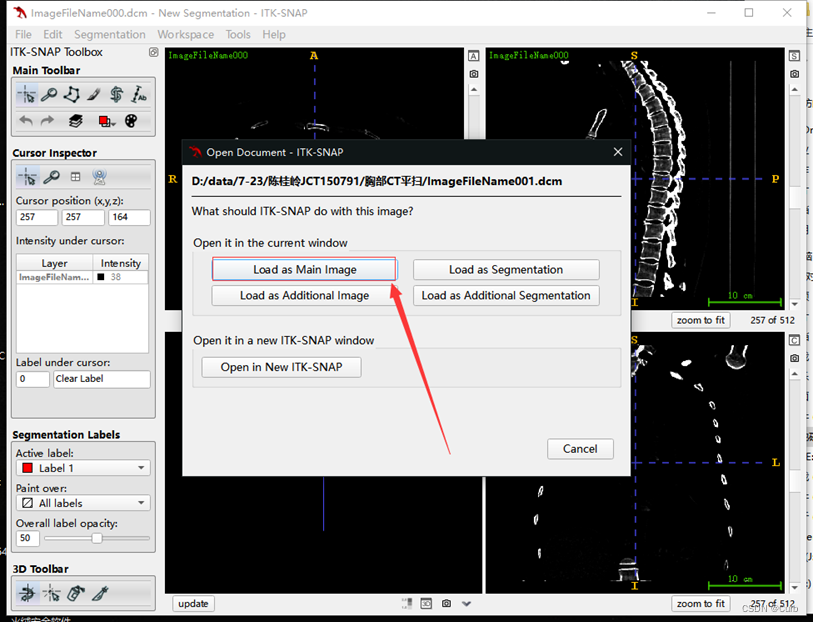

方法二:

采用直接拖动的方式

将右边文件夹中其中一个.dcm文件拖拽到ITK-SNAP中

选择Load as Main Image即可